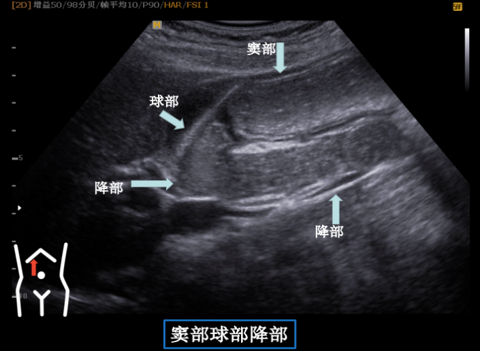

▲口服助影剂充盈后可清晰显示十二指肠各段